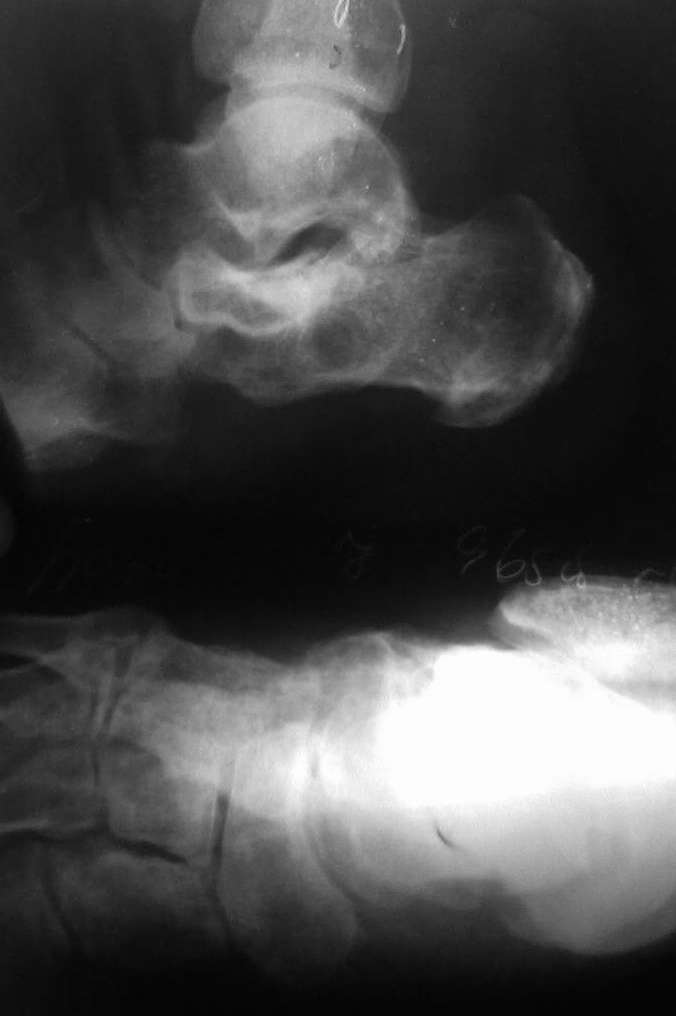

1. артродезировать задний(за исключением голеностопа) и средний отделы стопы в один этап - насколько это оправдано у пациента 43 лет, при том что на представленных преоп. рентгенограммах таранно-ладьевидный сустав сохранный?

2. Угол пяточной инклинации остался близким к горизонтальному,что за остеотомия была?

3. Из-за отсутствия продольного свода стопы и выполненных артродезов весьма вероятно быстрое развитие остеоартроза голеностопного сустава... что будете предлагать пациенту тогда?

1.Это тройной артродез и эта операция делается в один этап независимо от возраста, на пред/опер Р-грамме да и клинически имеется артроз таранно-ладьевидного и пяточно-кубовидного суставов с болевым синдромом,( из анамнеза плоскостопие 2-степ.)

2.Угол пяточной инклинации был и правда "остался" как было до операции, требование б-ного исправить только варусную деформацию, чтобы мог одеть обуви, правильно и б/болезненно наступать ногу, на одновременной исправлении плоскостопии несогласился.

Произведена клиновидная остеотомия пяточной кости, с обрашением основания клина кнаружу по скиаграмму из Рент аксиальной проекции.

3.При плоскостопии артроз г/стопного сустава не наступает, обычно страдает средний отдел стопы-как сустав Шопара, именно поэтому и произведена артродез данного сустава.